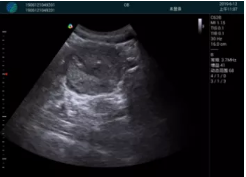

腺體內(nèi)部清晰顯示一低回聲塊影,形態(tài)不規(guī)則,邊界模糊,邊緣呈毛刺狀,內(nèi)部見砂礫樣鈣化

M20引導下穿刺活檢術(shù)

M20引導下平面內(nèi)穿刺取出的腫塊組織